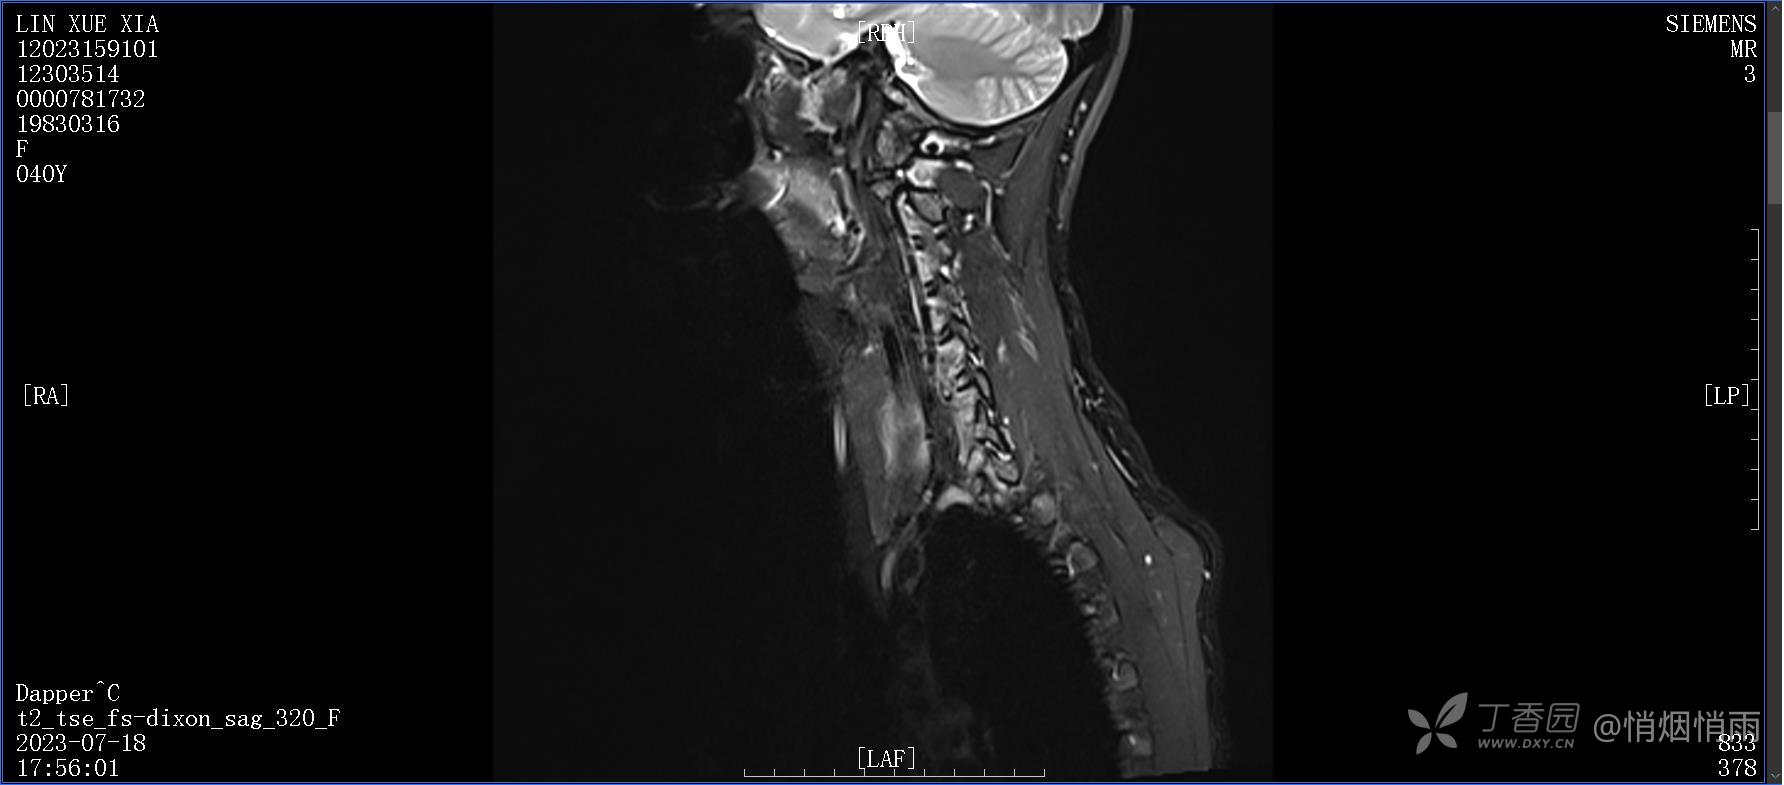

NeurothinkerZ 推荐患者女性,40岁,因右肩背部疼痛班活动受限4日余入院(2023-07-17)。

病史:入院前4天无明显诱因突然感右肩背疼痛伴随活动受限,自行口服依托考昔、艾瑞昔布等药物治疗,院外应用肩关节局部手法按摩等,均无明显改善。外院门诊诊为颈椎病。自诉既往多次“胸椎小关节紊乱”于当地诊所行手法按摩,治疗后好转,否认慢性疾病病史、外伤史、手术史,诉青霉素过敏,无其他药物食物过敏史,否认吸烟史、饮酒史,月经正常,经量正常。

目前的诊断,暂时依据辅助检查诊为肩袖损伤,但是患者疼痛的性质和特点,却不是单纯的肩袖损伤所致。考虑过胸廓出口综合征,但是该疾病会出现肩胛区的疼痛吗?(由于考虑到费用的问题,没再进行下一步的检查)带状疱疹会有如此的症状吗?